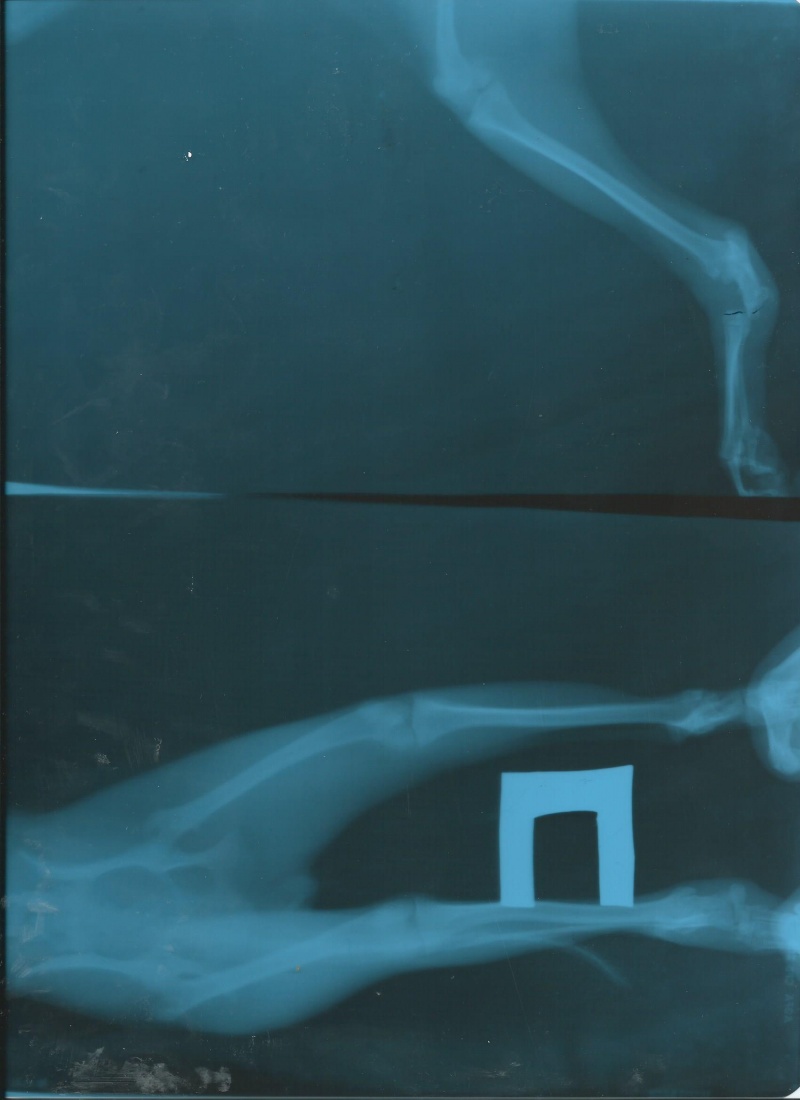

• Были у ветеринара. Отличный врач!!! Сделали снимок, наложили гипс. Перелома не было.На снимке хорошо видно лапку с вывихом.

• Вывих тазо-метатарзального сустава слева.